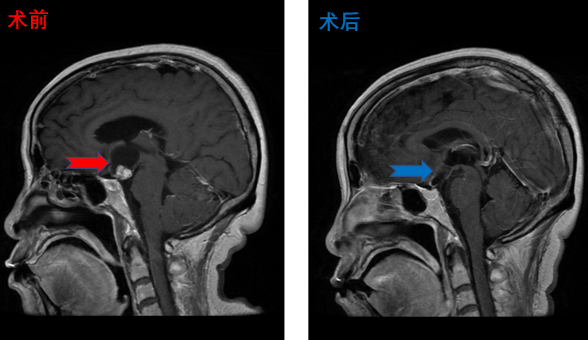

颅咽管瘤患者影像,患者术后视力明显改善,无明显尿崩及电解质紊乱